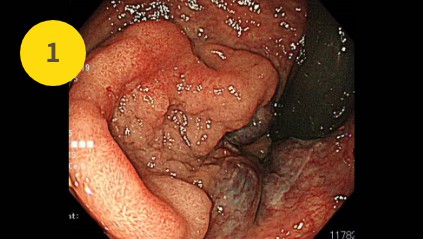

直腸の30mmの病変

直腸の30mmの病変です。病変も大きく、また一部はがんの可能性もあります。痔核も病変に接しておりESD(内視鏡的粘膜下層剥離術)が必要な病変と診断しました。